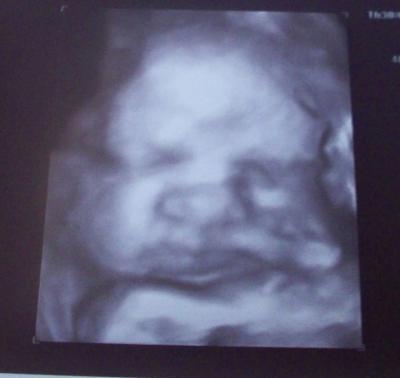

Heute kann ich auch mal wieder was berichten. Ich war heute zum Geburtsplanungsgespräche im KH. Der Oberarzt war mit uns ganz Zufrieden (ich zitiere: ein Kind mit Maßen wie aus dem Lehrbuch). Unser Moppelchen (siehe Bild) wiegt ca. 2950 g und ist 51 cm. Alles ist noch gut durchblutet und sie liegt noch über dem Becken. Die Senkwehen fehlen jetzt noch zum reinrutschen. CTG ohne Auffälligkeiten. Langsam realisier ich nun, dass es in gut 3 Wochen ernst werden kann. Ich lass aber alles ruhig auf mich zukommen. Das Gespräch mit dem OA war für mich eigentlich sehr beruhigend und meine Fragen konnten alle beantwortet werden. Für alle noch eine schöne Kugelzeit und für alle mit Baby auf dem Arm eine schöne Kuschelzeit. LG Kathleen

Bild zu Gutes Geburtsplanungsgespräch - Forum für Oktober - Mamis